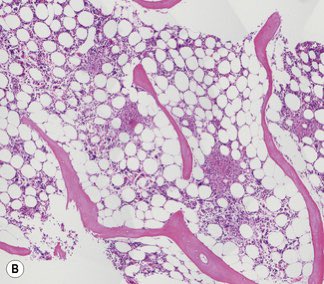

Bone marrow Biopsy

هي خزعة نخاع العظم او قطعة النسيج العظمي الاسفنجي نفسه 🦴

راح تروح على معمل الهيستوباثولوجي وهناك يتم التعامل معاها وتحضيرها وصبغها

وفحصها تحت المايكروسكوب لتحديد الاتي 🔽

📌cellularity

تحديد حجم الخلايا مقارنه ببقية مكونات نخاع العظم زي خلايا الدهون واذا كانت طبيعية مقارنه بعمر المريض